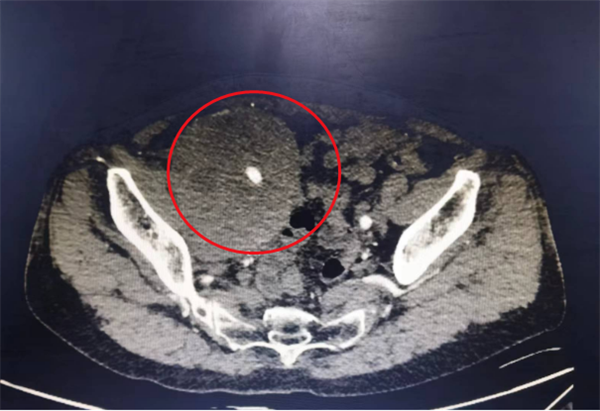

医学影像下陈女士身上的肿瘤清晰可见